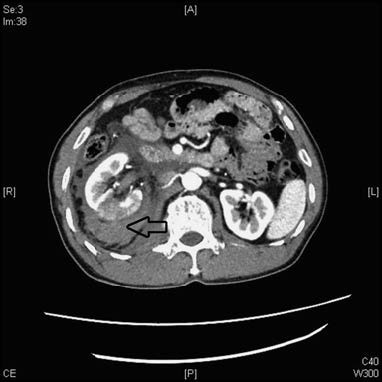

- CT: Non-contrast and contrast-enhanced CT effectively visualize the degree of renal parenchymal laceration, the extent of urinary extravasation and hematomas, renal perfusion, and the relationship with other organs. Contrast-enhanced CT is considered the gold standard for imaging the genitourinary system in renal injuries. CT urography (CTU) can identify reduced contrast excretion in the damaged kidney and detect contrast extravasation. CT angiography (CTA) facilitates assessment of renal artery and parenchymal damage and detects renal arteriovenous fistulas or traumatic renal artery aneurysms. Complete obstruction of the renal artery suggests traumatic thrombosis.

Figure 2 CT imaging of renal injuries.